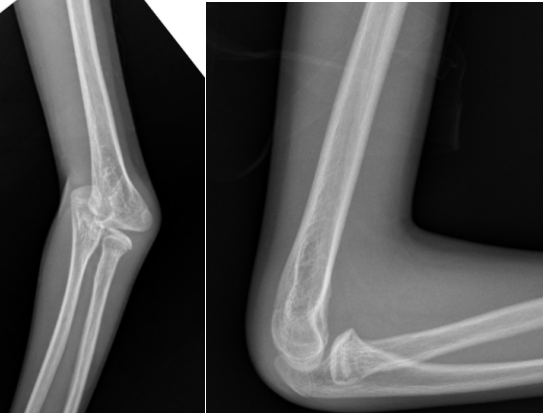

病例2:小红(化名)、女、9岁,3年前因摔伤致“左肱骨髁上骨折”,于当地诊所行手法复位夹板外固定,夹板固定一个月拆除外固定后逐渐发生左肘内翻畸形。

受伤当时的X线片

拆除夹板后的X线片

该例患者初始骨折为尺偏型肱骨髁上骨折,该种类型的骨折发生肘内翻畸形的可能性很大,需要在麻醉下手法复位纠正骨折端的尺偏移位,结合经皮克氏针固定,从而最大程度降低肘内翻畸形的发生率,但是当地诊所只是使用小夹板外固定,该固定不牢靠,骨折端容易再移位,且骨折端的尺偏移位纠正不足,种种原因引起了肘内翻畸形。针对该病例我们选择截骨矫形手术。